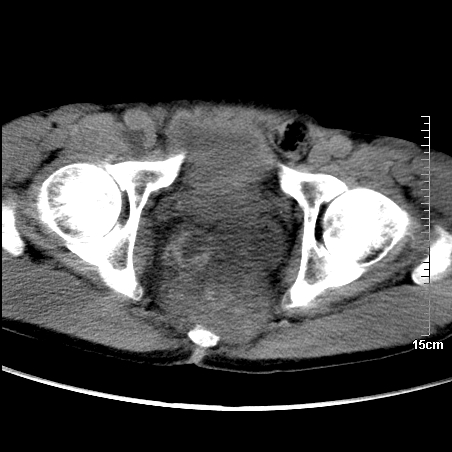

平扫:

部分骶尾骨已被软组织密度的肿瘤所取代,同意“首先考虑脊索瘤,不除外转移瘤”的意见。

1、骶尾部巨大软组织肿块,部分骶尾骨以被软组织肿块代替,呈不规则侵蚀;病变突向盆腔内;增强扫描病变呈不均质强化;首先考虑脊索瘤。不支持的一点就是病变内无钙化。